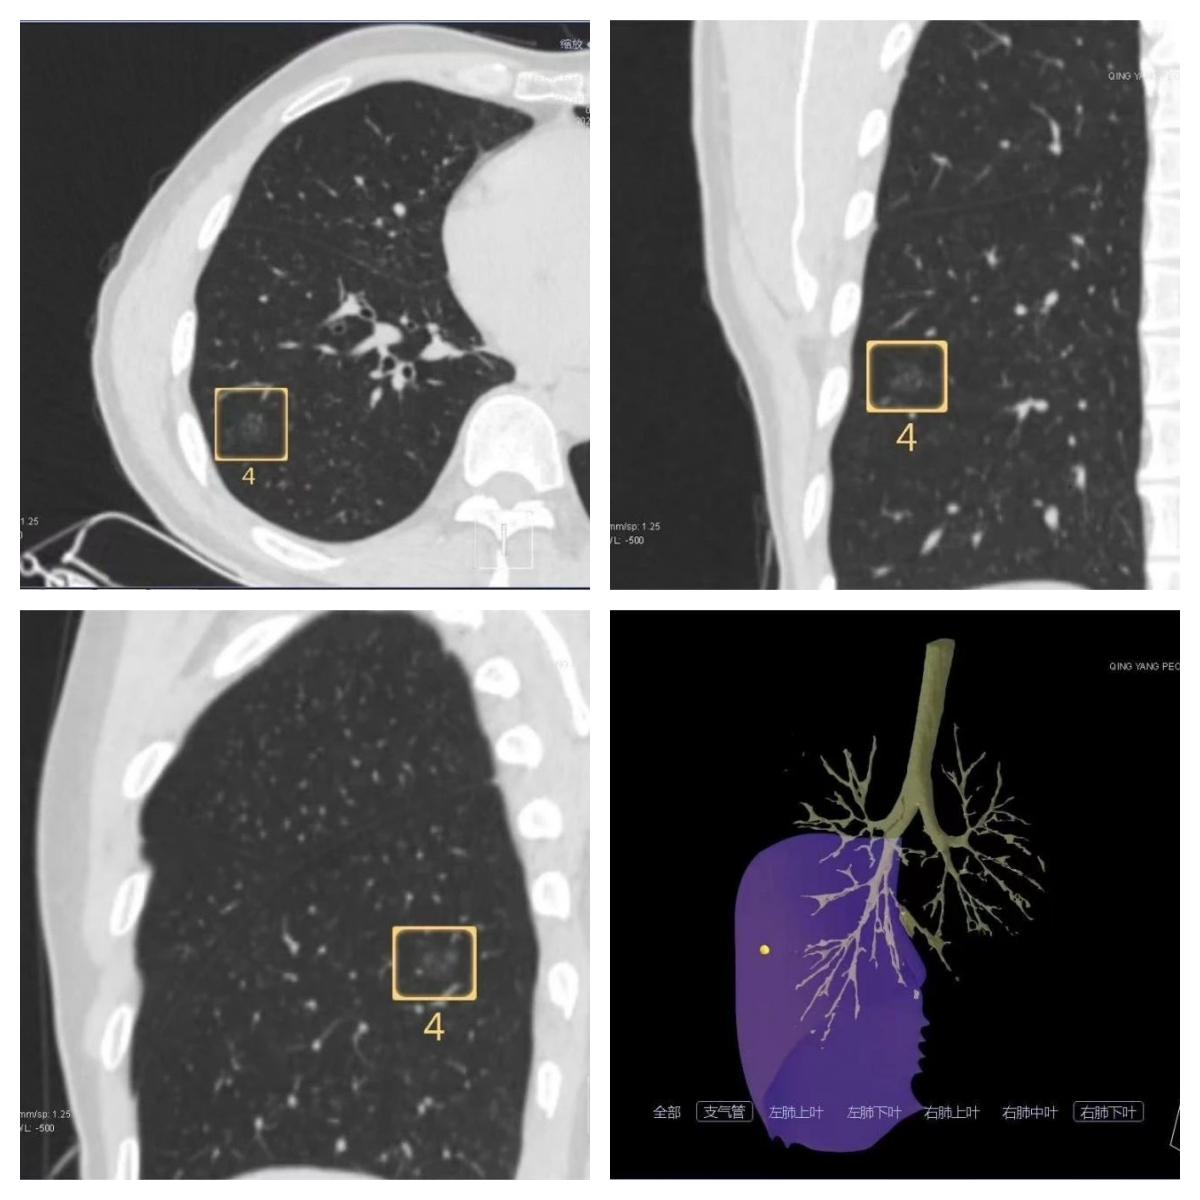

病例CT扫描,肺小结节病变三维重建

在胸腔镜肺小结节手术前,由医学影像中心团队应用CT引导实施肺穿刺,推注标记物“弹簧圈”,将“弹簧圈”头端钩于肺小结节病灶处,尾端留于肺表面,进行辅助定位,以便外科医生在术中根据标记物范围实施肺小结节精准切除。

CT引导肺结节穿刺定位